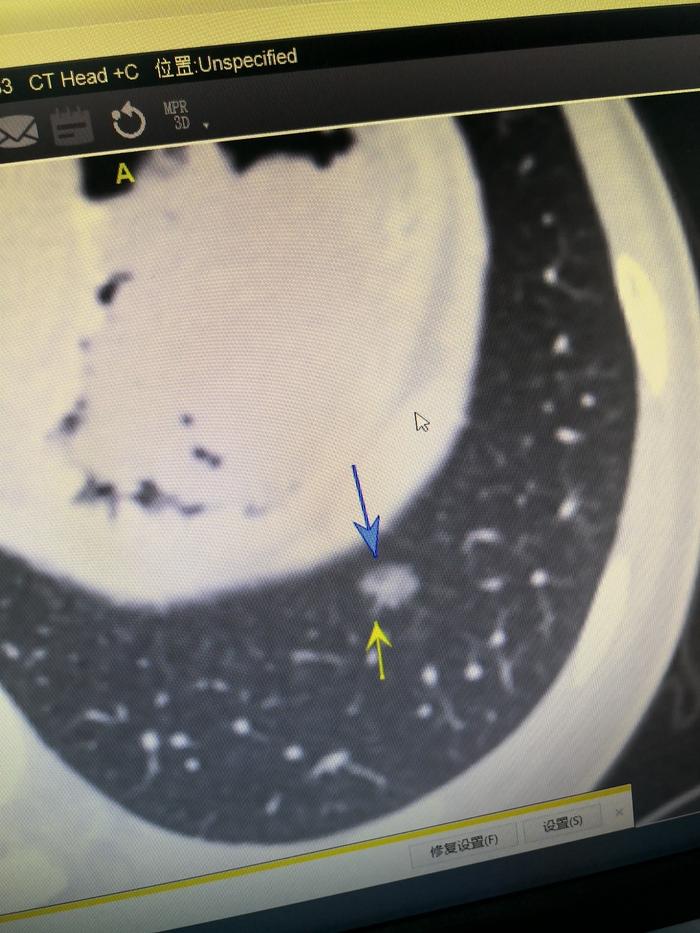

上图是手机拍摄的电脑屏幕。可以看到蓝色箭头指示的是结节内部偏前方一个圆形低密度区,看起来黑一些,就是一个小空泡。黄色箭头指示结节外面的一根毛刺影。

总体上,这是一个混合磨玻璃结节,实性成分相对较多,占比接近15%。结节有偏心小空泡,有毛刺影,密度不均,是一个典型的恶性磨玻璃结节。术前判断恶性的几率大约95%左右。术前和丈夫签字时,我说:“估计病变基本上是肺癌,应该超过原位癌阶段,因为原位癌一般是纯磨玻璃结节,病变估计到了微小浸润性腺癌的阶段,估计病变到浸润性癌的可能性不大。结节有一定实性成分,以后会越长越快。如果到浸润性腺癌阶段就可能转移扩散。我在医患沟通表上写明结节为微小浸润性腺癌可能大。”家属同意手术。